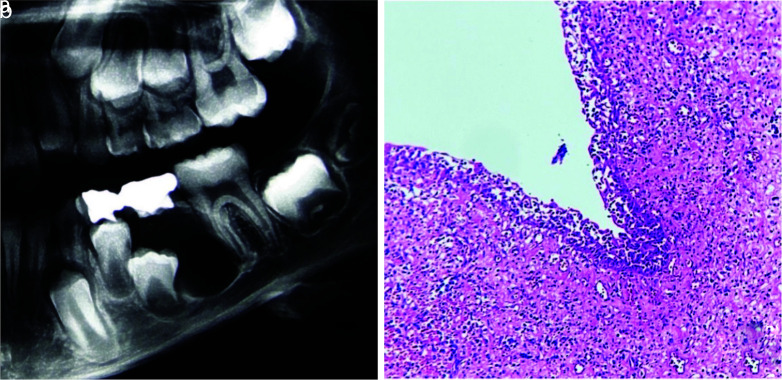

Results:  In the present study, 474 cases were diagnosed with a periapical cyst/granuloma clinico-radiographically, of which 61 cases (12.86%) received a microscopic diagnosis of a non-endodontic pathology. The most frequent lesion was odontogenic keratocyst (n= 12, 19.67%) followed by infected odontogenic cyst (n= 12, 19.67%). About 21.31% of diagnoses were non-cystic lesions and 4.9% were malignancies. The most odontogenic tumors that were diagnosed as periapical cyst/granuloma in clinico-radiography were the ameloblastoma variants (n= 4, 6.55%).

Conclusion:  A wide variety of microscopic diagnoses, including aggressive lesions such as ameloblastoma, as well as other malignant lesions was noted in this study. These misdiagnoses can lead to an inappropriate treatment plan. It is important to microscopically examine all lesions removed from the jaw.

Abstract Image